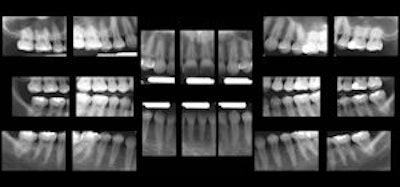

![]() ![]() Click here to enlarge these images. |

"Dr. Langlais, a highly respected oral and maxillofacial radiologist, is interested in something we are all interested in: finding a way of detecting caries without having to place something in someone's mouth," said Don Tyndall, D.D.S., M.S.P.H., Ph.D., director of oral and maxillofacial radiology at the University of North Carolina at Chapel Hill School of Dentistry, in an interview with DrBicuspid.com. "Dr. Langlais has stated in his textbook on panoramic radiology that panoramic imaging is equal to intraoral bitewing images for detecting caries. Unfortunately, at this time there is no published research that scientifically validates this claim. So while I applaud the idea of extraoral caries detection, and it is worth pursuing, I don't think there is any scientific evidence yet to show there is anything better at this point than intraoral radiography."

However, Dr. Tyndall added, "I do believe panoramic-based bitewings are a step in the right direction."